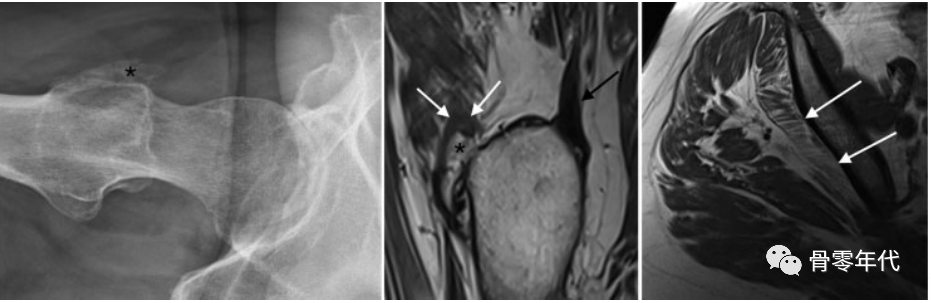

(a)一位74岁女性的右侧髋关节侧位X线片显示臀小肌腱附着处有一个大的突起(星号)。(b)重度臀小肌腱病(白色箭头),在矢状面T1加权像上插入末端(星号):仅有轻微的臀中肌腱病(黑色箭头),伴有微小的末端隆起。(c)轴位T1加权图像显示臀小肌严重脂肪变性,最明显的是后部和中部(白色箭头)。